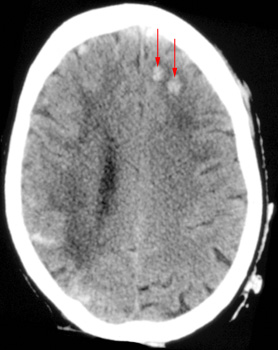

Question 6: Given the following head CT, the most likely diagnosis is: